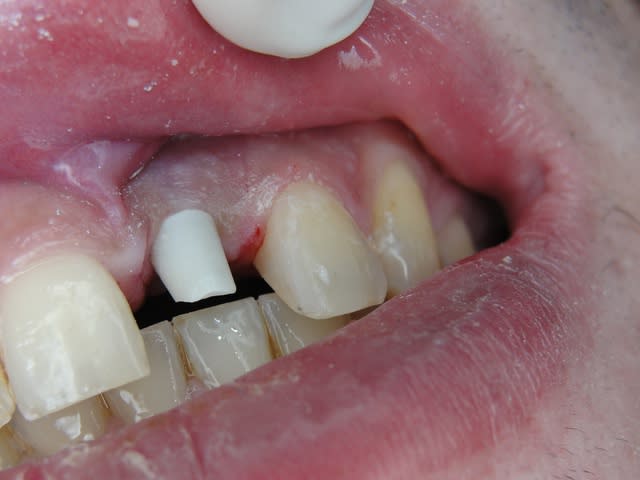

J'ai de tout en boutique..jeune homme 25 ans accident de piscine choc sur la bordure ( fêlure existante..fistule), extraction le jour même, temporisation 4 mois (avec un bout de trombone) Monobloc 16mm 60N, prep cap zircone droit 2/2 provisoire ion, temporisation 3 mois ceramo ceram..

J'ai de tout en boutique..jeune homme 25 ans accident de piscine choc sur la bordure ( fêlure existante..fistule), extraction le jour même, temporisation 4 mois (avec un bout de trombone) Monobloc 16mm 60N, prep cap zircone droit 2/2 provisoire ion, temporisation 3 mois ceramo ceram.. suite des photos :)